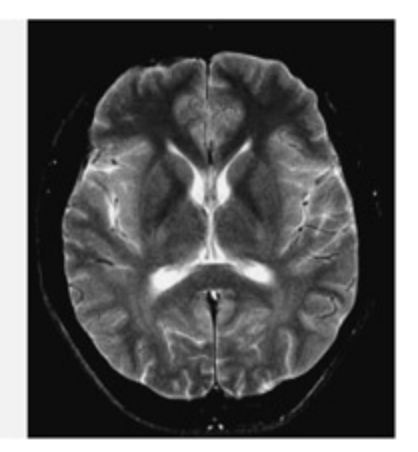

📊 그림 설명

T2-가중 MRI 뇌 스캔 이미지이다. T1-가중 영상과 달리 조직의 T2 이완 시간 차이를 반영하며, 뇌척수액이 밝게 나타나는 특징이 있다. T2* 성분은 탈산소화 헤모글로빈에 민감하여 fMRI의 BOLD 신호 측정의 기초가 된다.

An example of CT (le), T1-weighted MRI (center), and T2-weighted MRI (right) scans of the brain. Note how the MRI scans are able to distinguish between gray maer and white maer. On the T1 weighted scan (normally used for structural images), gray maer appears gray and white maer appears lighter.

Different types of image can be created from different components of the MR signal. Variations in the rate at whi the protons return ba to the aligned state following the radio frequency pulse (called the T1 relaxation time) can be used to distinguish between different types of tissue. ese T1 weighted images are typically used for structural images of the brain. In a T1-weighted image, gray maer looks gray and white maer looks white. When in the misaligned state, at 90 degrees to the magnetic field, the MR signal also decays because of local interactions with nearby molecules. is is termed the T2 component. Deoxyhemoglobin produces distortions in this component and this forms the basis of the image created in functional MRI experiments (called a T2* image, “tee-two-star”).